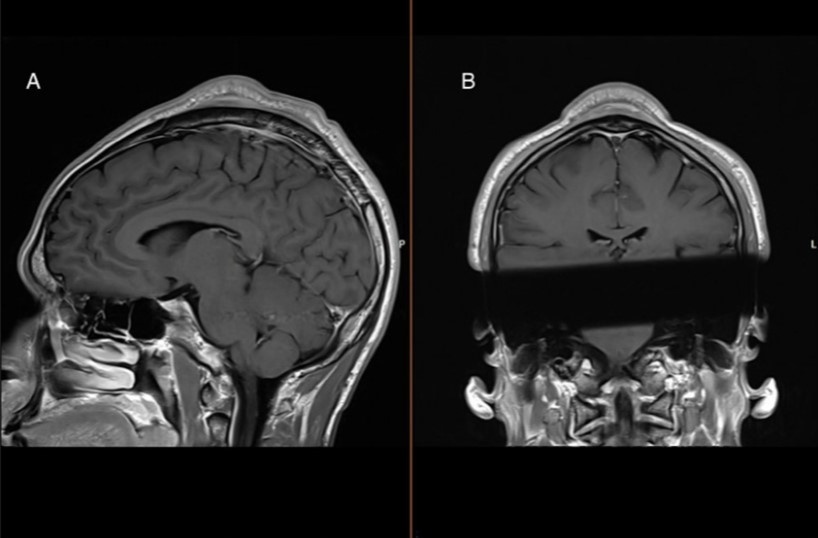

При клиническом осмотре на макушке, по средней линии, было заметно продольно ориентированное образование. При касании опухоль была болезненной, не спаяна с кожей. Это позволило врачам предположить, что она находилась под сухожильным шлемом головы. Магнитно-резонансная томография показала образование под сухожильным шлемом размером 33,4 × 0,6 × 2,9 сантиметра вблизи срединной линии с сосудистыми структурами. Кожа и подкожная клетчатка над опухолью были утолщены, так же, как и кость черепа под опухолью.